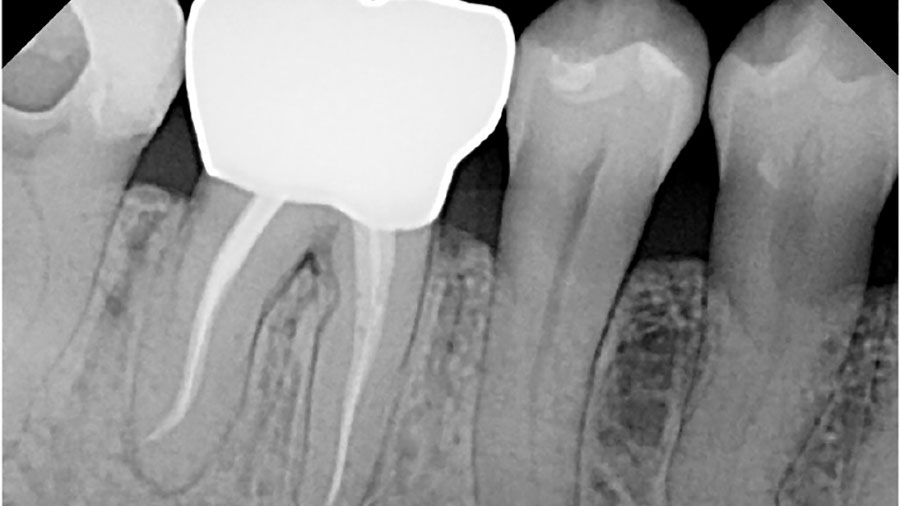

Lasers in Endodontics

Comments from Maarten Meire re; subject about to get a lot of press as Biolase Technology has secured a new patent for cleaning and disinfecting root canals. The new patent called “Fluid Controllable Laser Endodontic Cleaning and Disinfecting System” covers the use of an endodontic probe loaded with cleaning particles/agents and measuring kit to clean … Read more